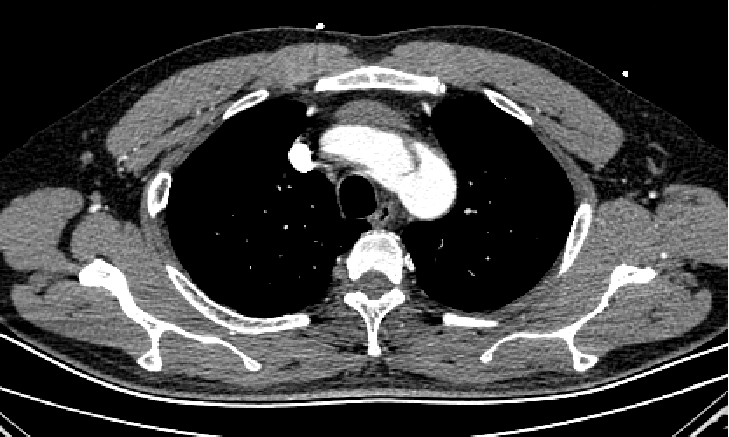

男, 49岁,急性夹层 。2018年11月TEVAR。一月后复查:RTAD 。 2019年1月双开窗。2019年4月2日 复查,结果良好。

▎病例五